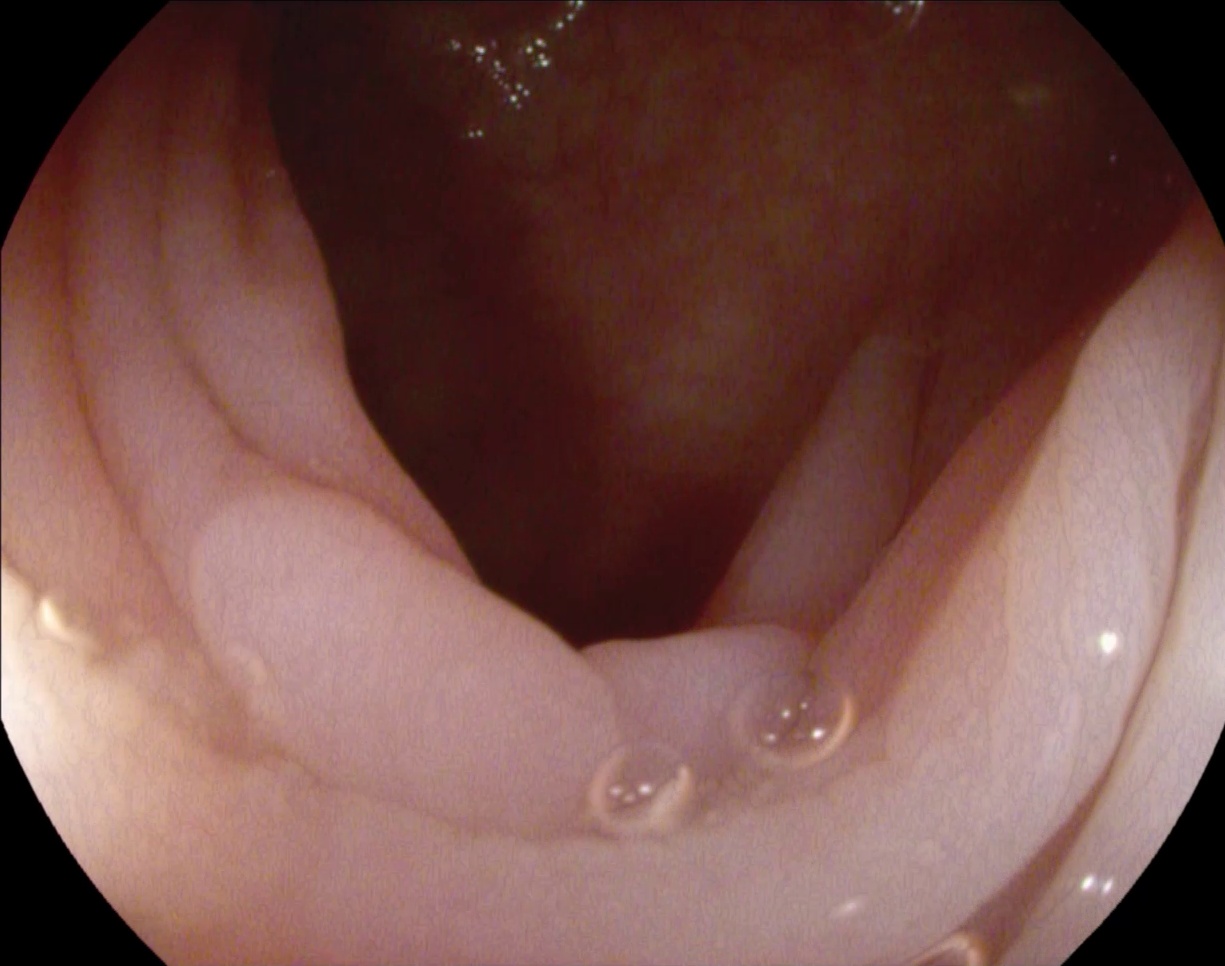

该数据库专为结直肠癌早期筛查提供高质量医学影像数据。该数据库汇聚了丰富的高分辨率内窥镜影像。这些影像经过严格的质量控制流程,并被用来优化自动化诊断算法的性能。该数据库涵盖多种类型息肉及复杂内镜场景

处理好后的COCO格式的数据集图像的总数为380张,类型标签为病灶区域。